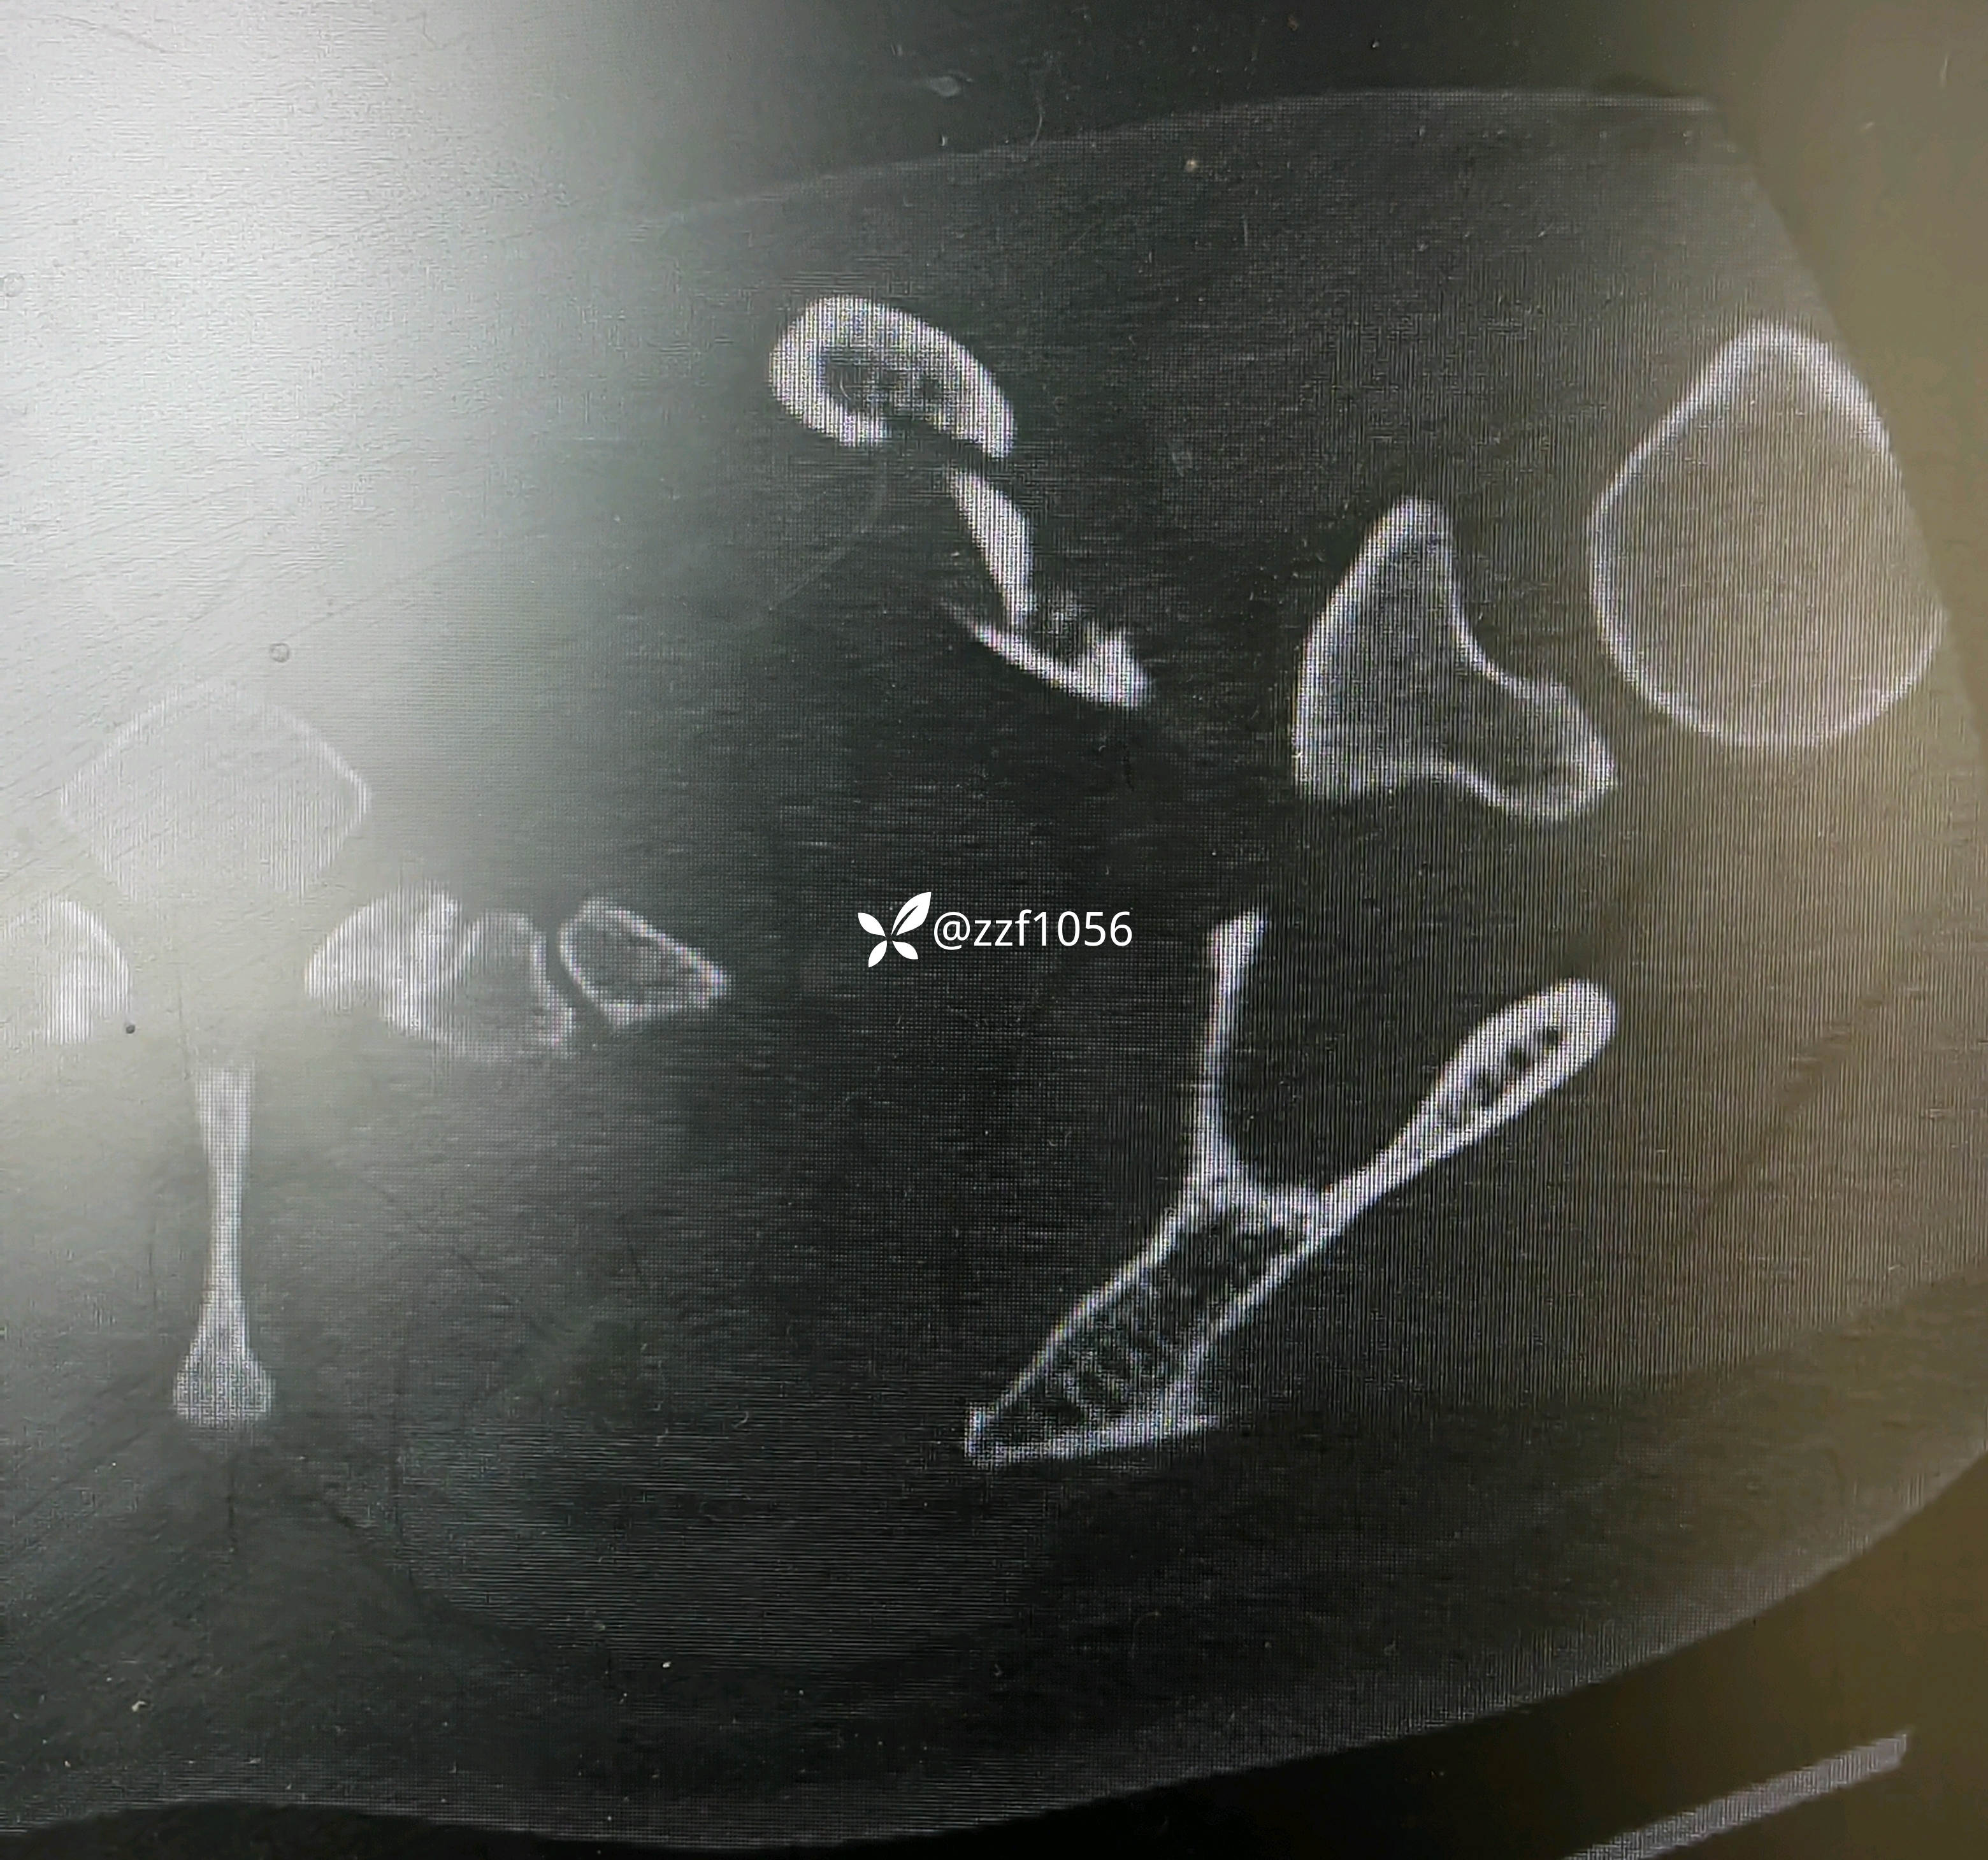

术中作切口后探查未见皮神经,保护好骨膜,清理折端复位临时克氏针固定,后方蝶形骨块较大,nice结改2道钢丝捆扎,复位良好,取最长10孔钢板,貌似钢板有点短,远折端3枚锁定螺钉有效固定,近折端只有2枚螺钉有效固定,第3枚螺钉失效且后方仍有骨块微翘,无奈增加一枚钢丝适宜捆扎。

2.骨折端跨度较大,接骨板偏短,会出问题吗?器械厂家告知这是最长锁骨钢板,貌似用过12孔,现在单用钢板器械商都不愿意发了。